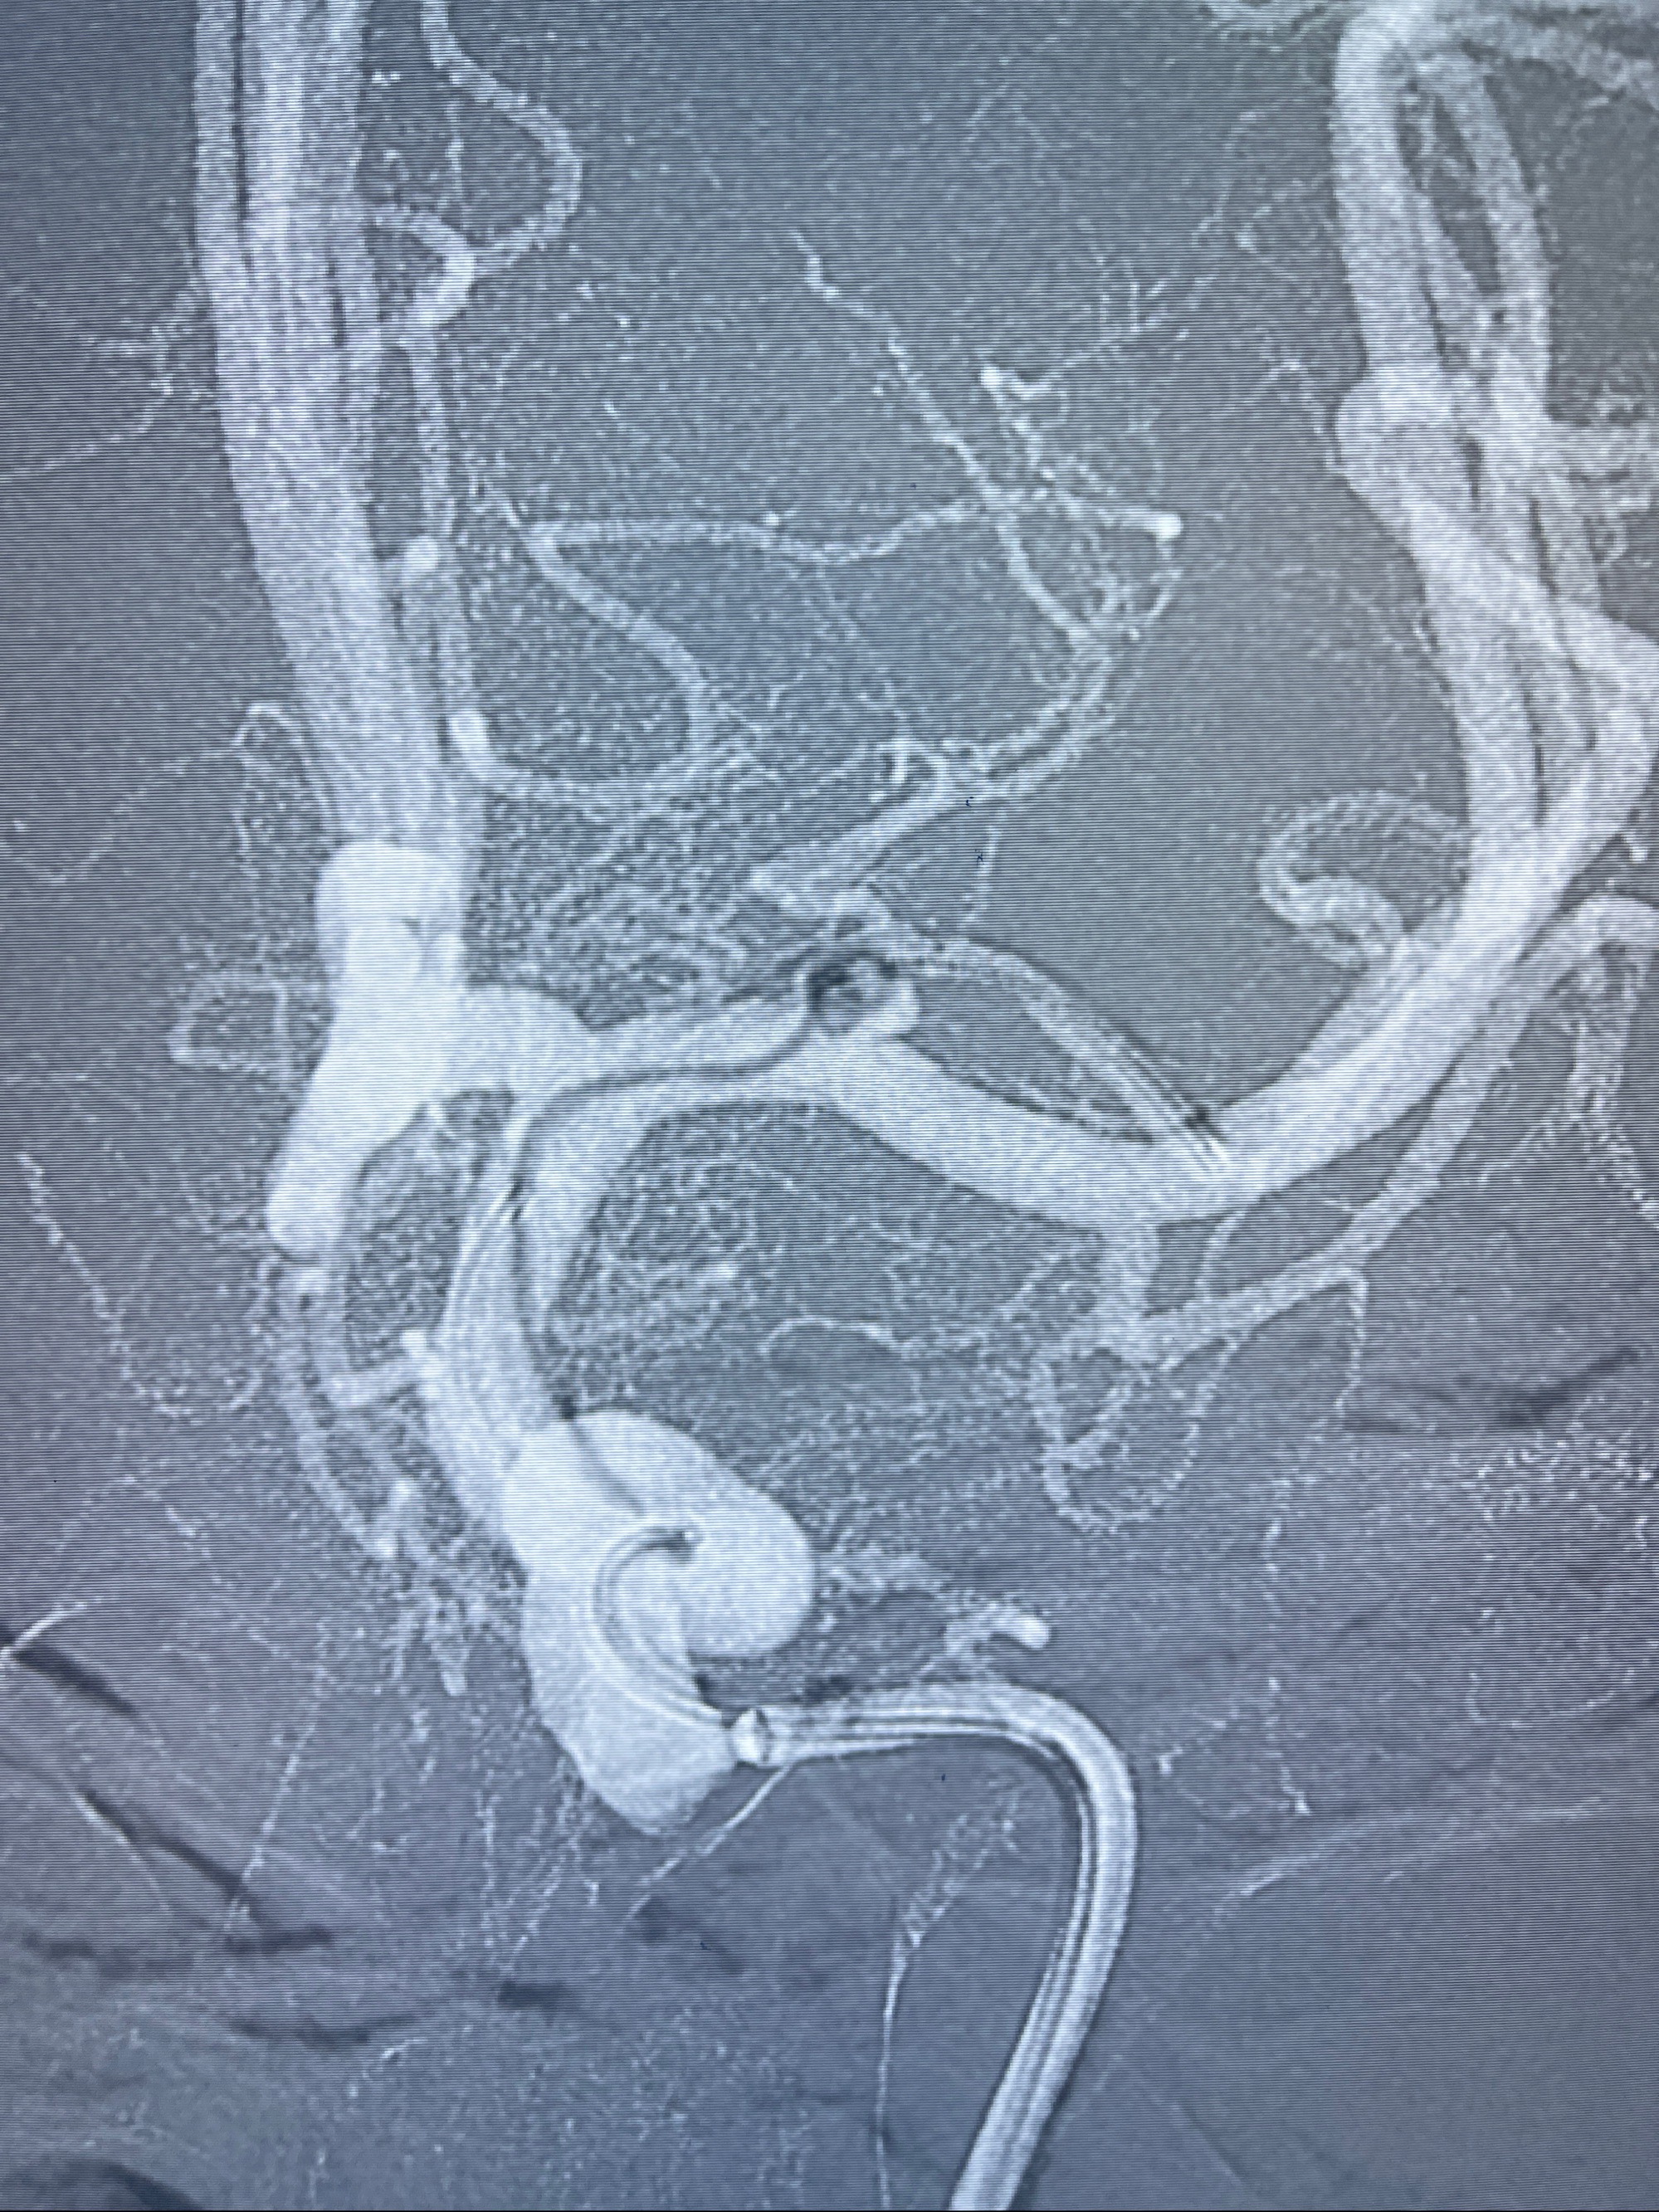

辅助检查:2023-07-12 上海大学附属第三医院 头颅CTA:左侧大脑中动脉M1段动脉瘤(1.7*3.4mm),右侧大脑前动脉A1段缺如,左侧椎动脉V4段纤细。

2023-08-14DSA:

左侧大脑中动脉动脉瘤,约2.6-2.8-3.4-2mm大小(瘤颈部、瘤体部、瘤高)

1.左侧大脑中动脉动脉瘤,约2.6-2.8-3.4-2mm大小(瘤颈部、瘤体部、瘤高)